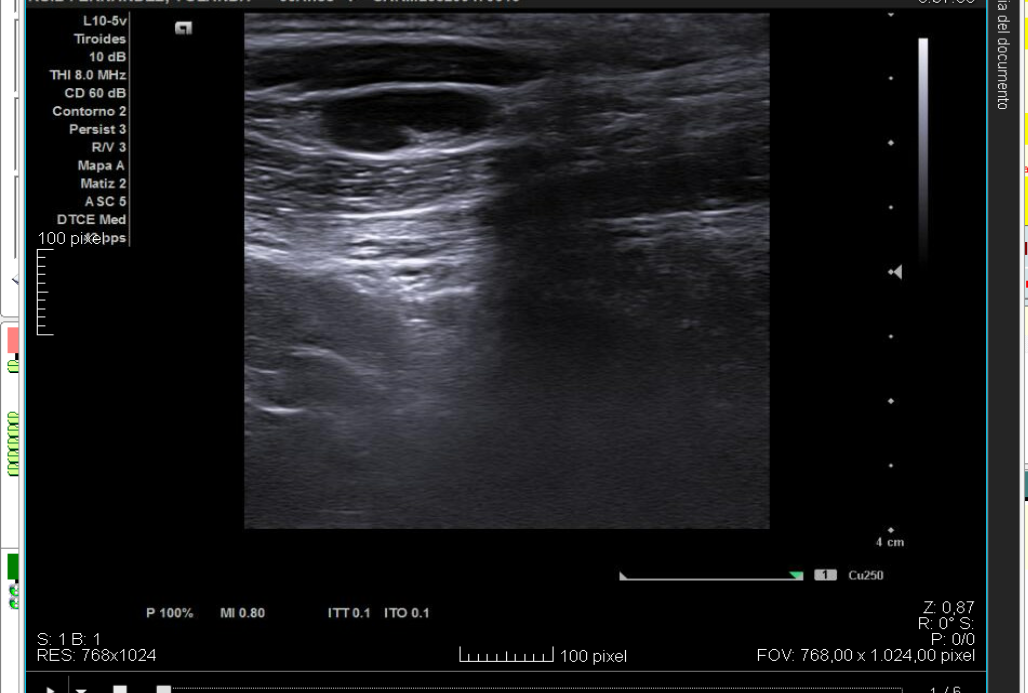

Se realiza ecografía en la consulta de AP (sonda lineal L10-5V). La gran mayoría son adenopatías subcentimétricas, con hilio central hiperecogénico y vascularización central. Se amplía estudio con analítica y una interconsulta a Hematología.

En la analítica se objetiva ligera leucopenia y neutropenia. Serología positiva para IgG frente a virus Epstein–Barr. Resto de parámetros normales, incluidas VSG y PCR. Tras 3 semanas se realiza nuevo control ecográfico, observándose cambios respecto al estudio previo: agrandamiento de adenopatías mayores de 10 mm, hipoecogénicas, en conglomerado, con pérdida del hilio y aparición de una adenopatía supraclavicular derecha de 14 mm con vascularización periférica. Estos hallazgos resultan sugestivos de proceso linfoproliferativo, por lo que se tramita derivación preferente a Hematología con solicitud de PAAF, que se realiza en 48 horas. Tras su valoración, la paciente ingresa para completar estudio.